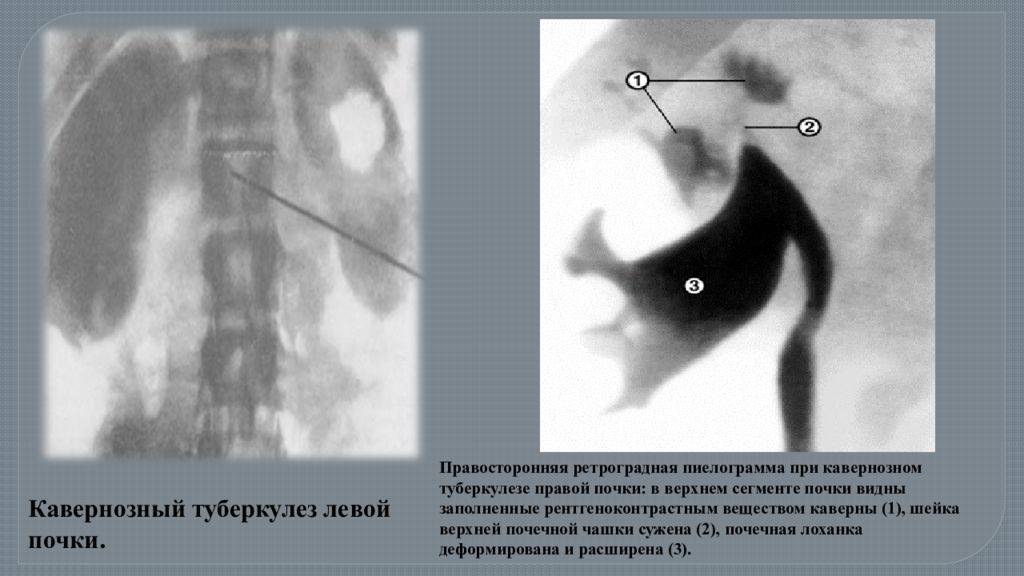

Понимание кавернозного туберкулеза почки